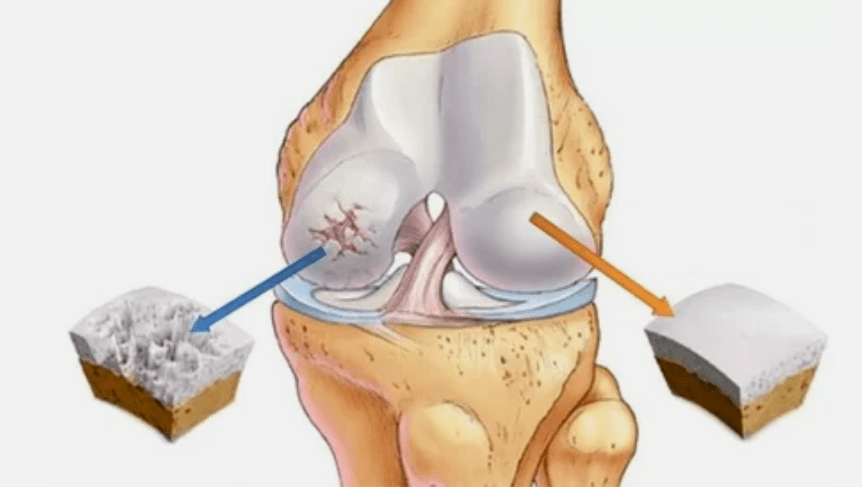

- Déi primär Läsion beaflosst den Hyaline Knorpel. Am Fall vun Terrard iwwerdeet, pathologesch Kraaftschued geschitt. Et ass den éischte Schrëtt oder Ursaach, wat kann arthroosis geschéien.

- Hyalin Coating Pathologien. D'Buedem vum Kuerplang féiert dem Ersatz vu senge placologeschen Tissiste:

- Anomalous Wuesstum erschéngen op Knorpelage - Osteophyten.

- D'Wieler vun der natierlecher Anatomie vum Knorpel a Schanken provozéiert d'Iwwerlaaschtung vu gesonde Beräicher vum Knorpel. D'Zersteierer er archikulär Tofsbletzungen ass dauernd dout zou a féiert zu Behënnerung.

Wann de Grad vun der Krankheet eropgeet, pathologesch Prozesser sinn nach ëmmer verschlechtert. Zum Schluss, all Hyalin Knorpel ass zerstéiert.